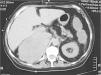

Mujer de 64 años con nódulo pulmonar e hipertensión arterial